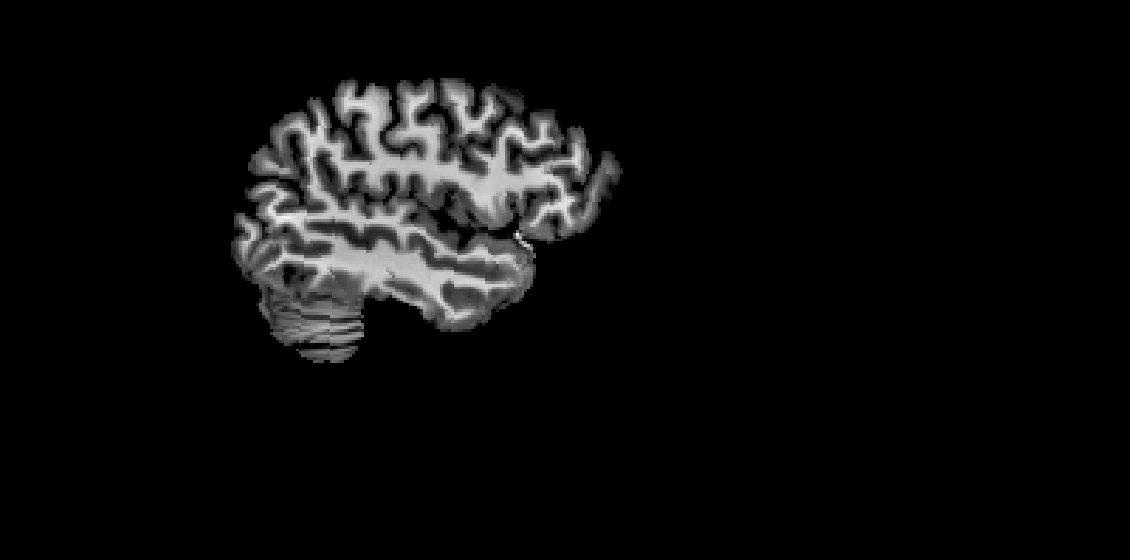

smriprep brain mask